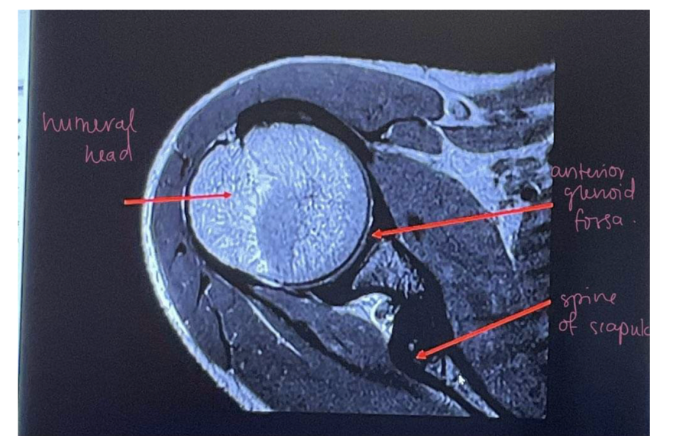

1. What MRI imaging plane best demonstrates the glenoid labrum?

1. • Axial (expand? or)

label